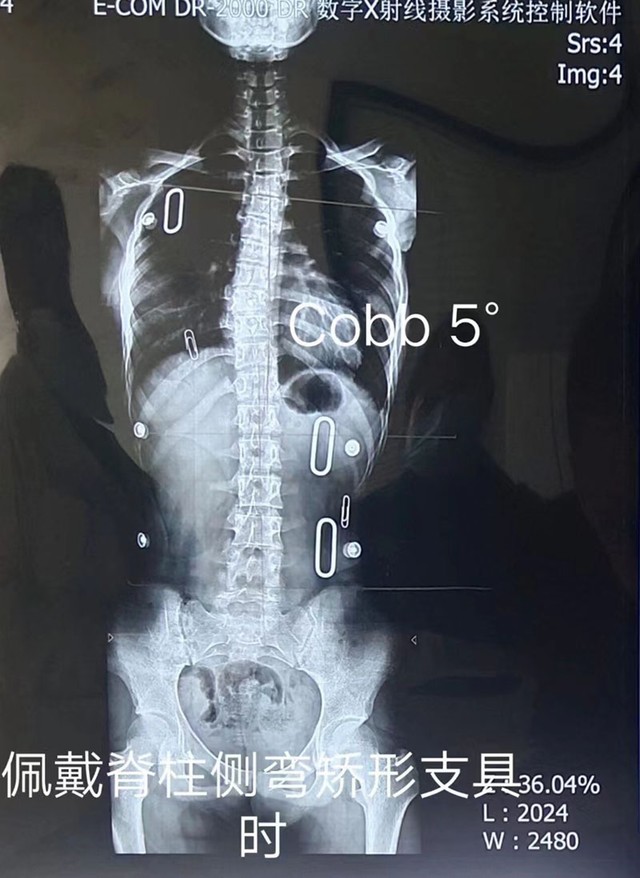

脊柱侧弯矫形器